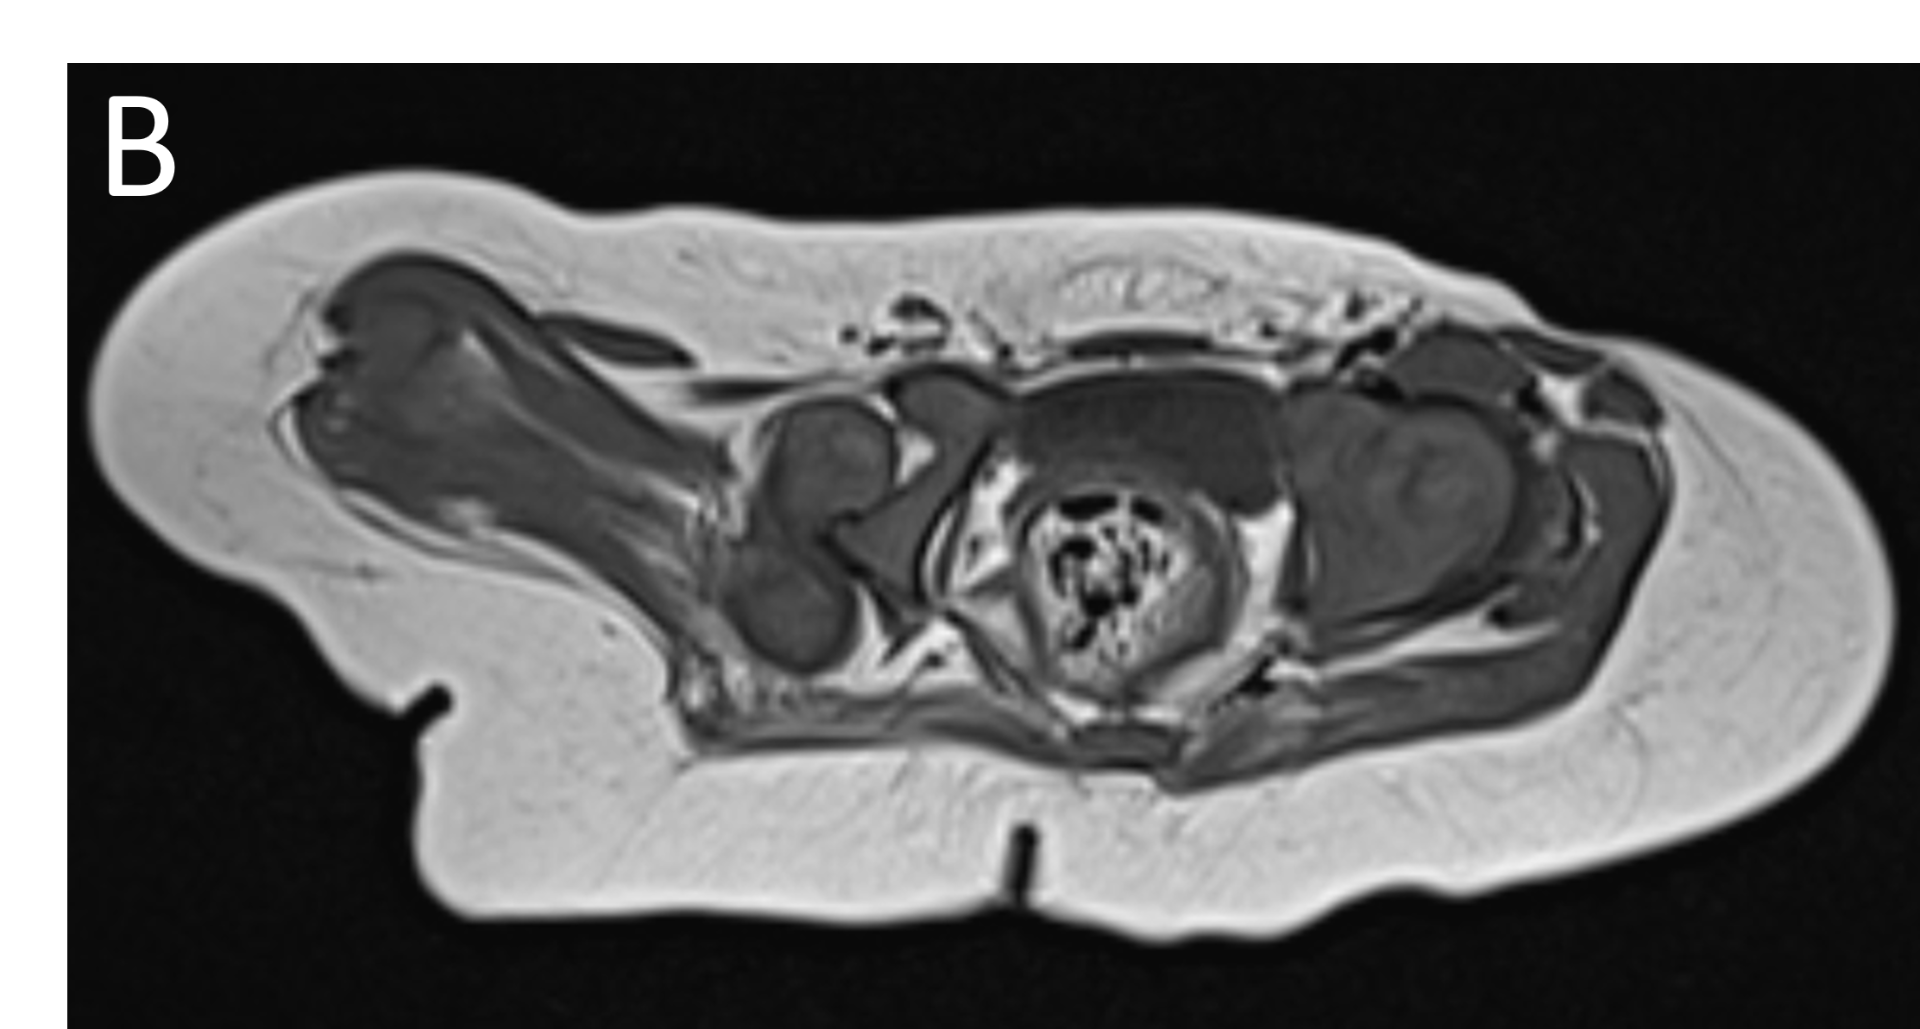

- B.LEGENDS – MR BILATERAL HIPS : Generalised atrophy of muscles of thigh and gluteal region on the right compared to the left.